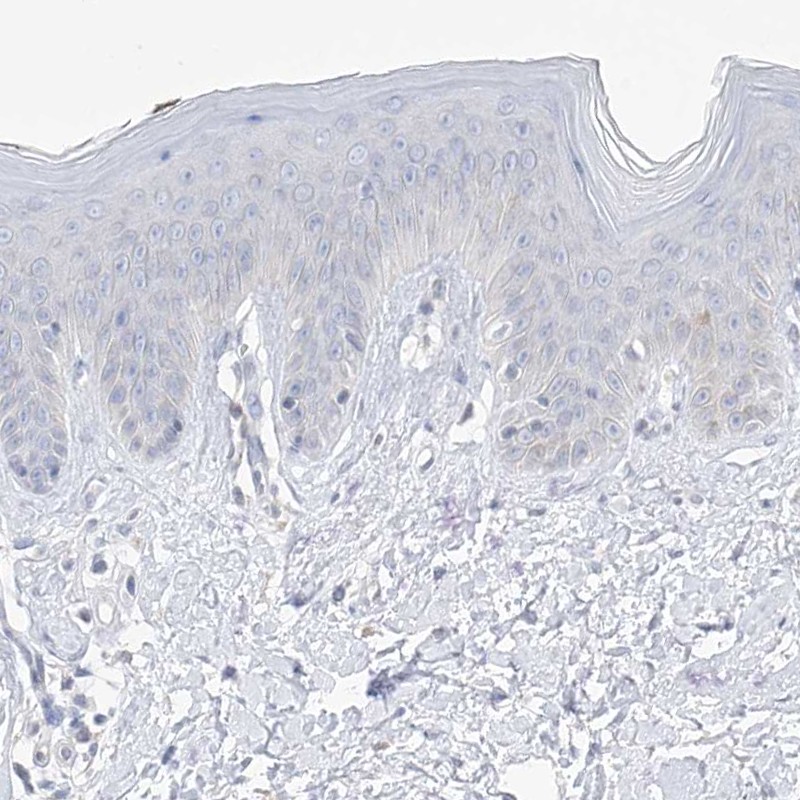

Immunohistochemistry analysis in human spleen and skin tissues using Anti-TBXAS1 antibody. Corresponding TBXAS1 RNA-seq data are presented for the same tissues.